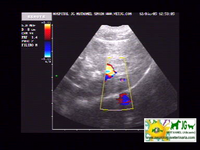

ecografía donde se aprecian las neoplasias hepáticas |

intentamos buscar el shunt portosistémico, pero no es visible ni con el doppler |

Se aprecia la vena porta muy aumentada de tamaño y sinuosa, por lo que es previsible que haya shunts, aunque no los distingamos |

video de ecografía con doppler: |